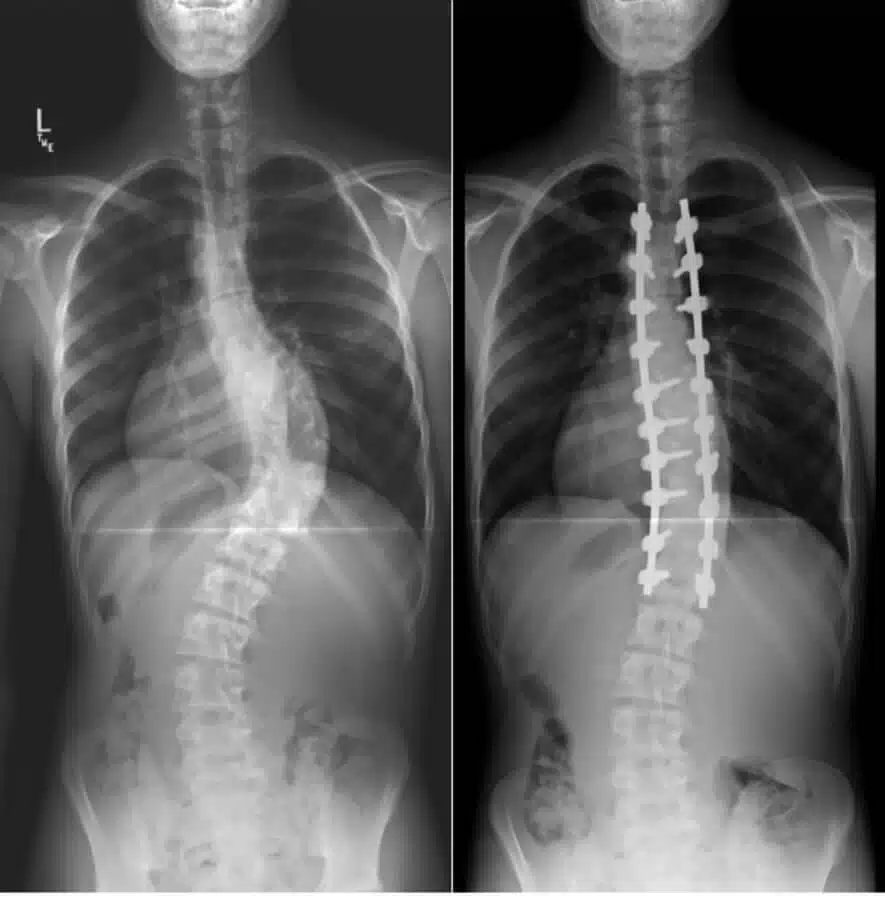

- Correct spinal deformities such as scoliosis (spine curve).

This procedure is done under general anesthesia. The surgeon makes an incision in your abdomen or your throat to be able to access your spine from the front. As previously mentioned, the surgeon uses the extra bone to fill the gap between vertebrates. Bone graft preparation is important to work. The surgeon can take it from a bone bank or it can come from your own body. The surgeon removes the disc material and facet joints. He/she may remove all facet joints or just part of them. Then he/she packs the space with bone graft. Then, the surgeon inserts screws, spacers and rods into the bones to hold everything in place temporarily.